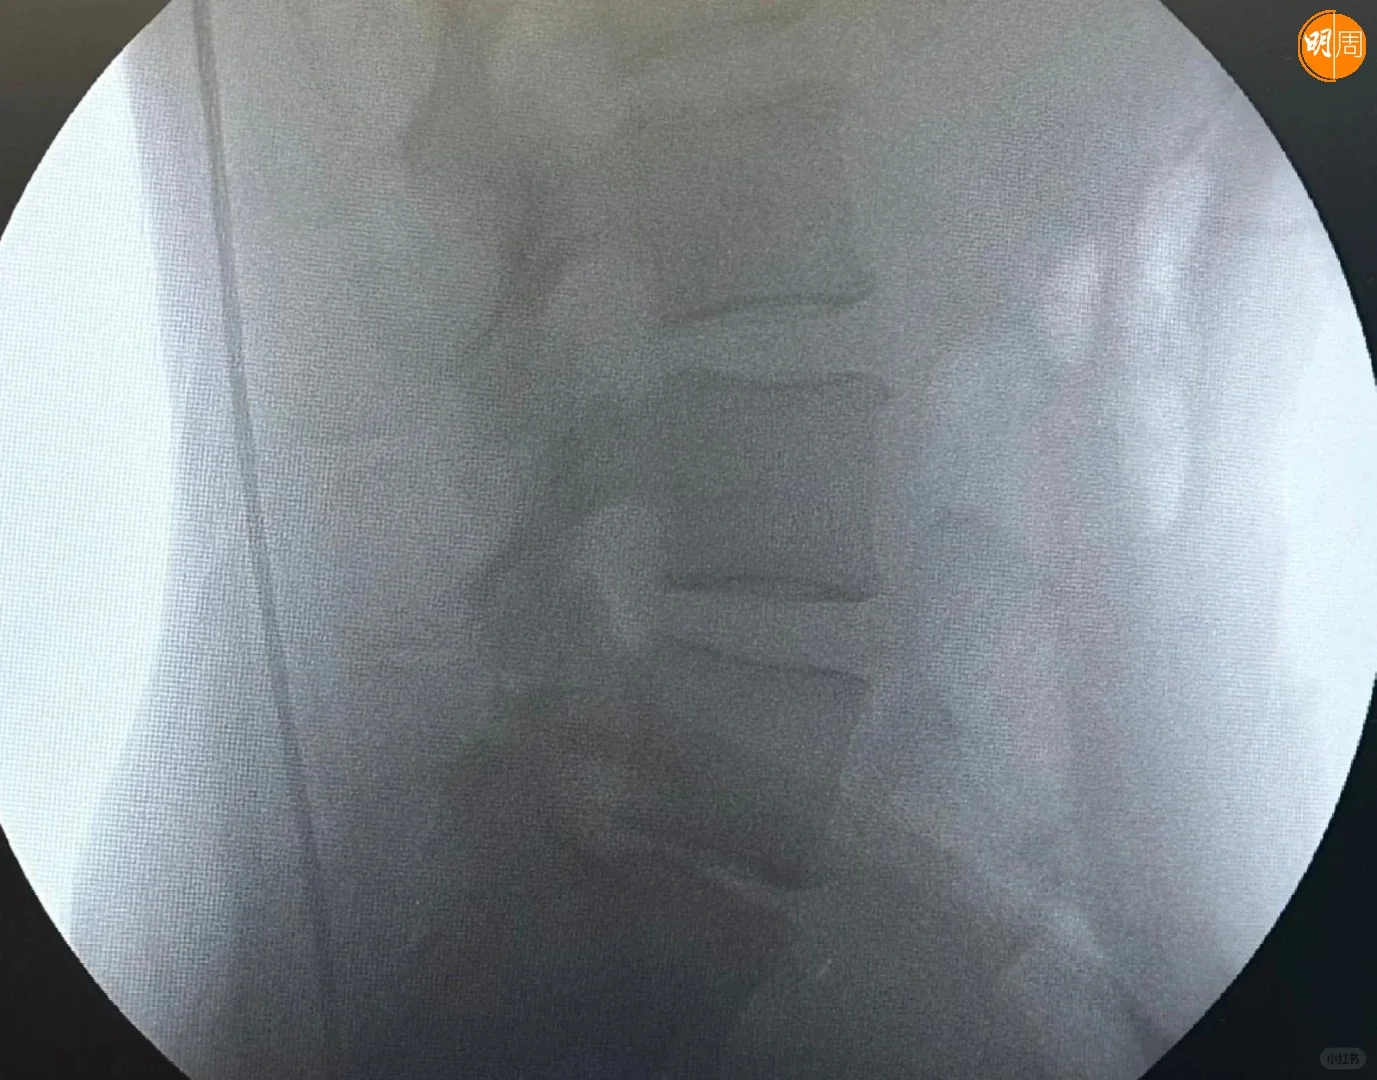

徐濠縈(阿徐)近日也入院做手術,昨晚(24日)阿徐在社交平台貼出X光照片,以及在手術室和醫護人合照,相中見阿徐露笑容,神情輕鬆,同時她上載花束及營養品等照片,此外,亦見到「加油!媽媽」的祝福句,似是囡囡陳康堤送給媽媽的打氣語句。

阿徐留言表示,今次是她自生女後最重要的手術,自揭前年曾接受切除椎間盤部分的手術,但下背仍然疼痛不已。熱愛跑步的她又謂,這2年過得特別難,她要停止重量訓練,並影響到她的日常生活,每當打噴嚏時,都有劇痛感覺,她的醫生建議做椎間盤置換手術。

阿徐今日(25日)亦有在小紅書發文,附加了臥在醫院病牀上雙手舉V的照片,她看來精神很好,身旁有到來探病的3大猛男謝霆鋒、馮德倫和劉浩龍,不知是否Eason負責揸機拍攝。阿徐以「手術成功」為題,並留言透露:「『人工椎間盤置換術』是一早安排今個6月份做的手術」、「康復時間需要幾個月」,網民都祝阿徐和Eason早日康復。